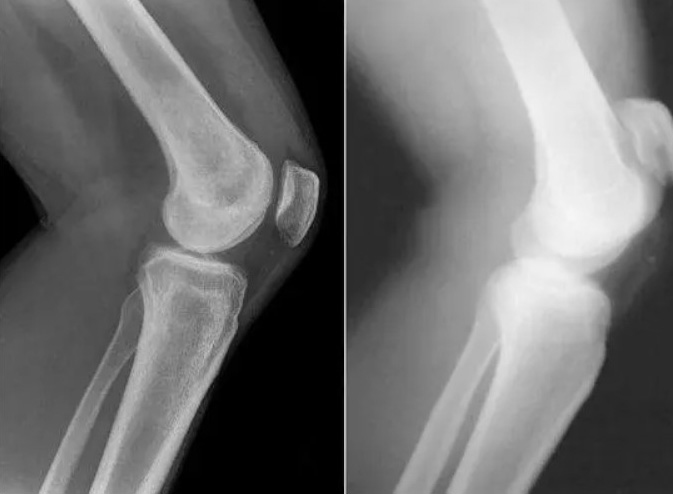

- Los osteofitos son sales calcificadas responsables del 97% de las demás enfermedades articulares y de la columna, como la artritis, artrosis, osteocondrosis, osteoporosis, reumatismo, bursitis e incluso quistes sinoviales.

Estas sales, al depositarse en la superficie de la articulación, actúan como papel de lija, dañando los tejidos circundantes, los huesos y el cartílago. A medida que los cristales crecen, comienzan a dañar los tejidos musculares, los tendones, los vasos sanguíneos y los capilares, provocando inflamación, infección, hinchazón y dolor intenso.

En los casos avanzados, grandes acumulaciones de estas sales pueden romper fácilmente una parte del hueso con un movimiento brusco, lo que lleva a una discapacidad total e inmovilidad permanente de la articulación.